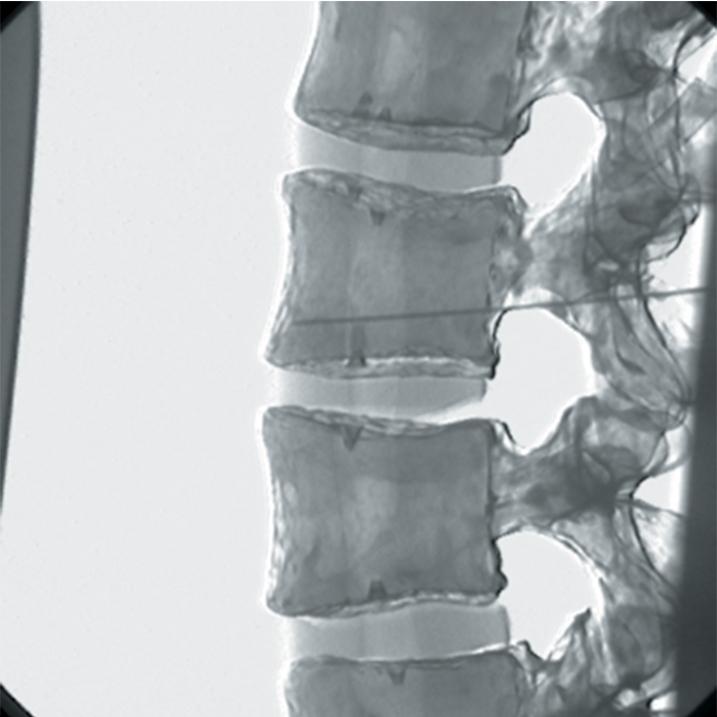

The Regional Anaesthesia Simulation Manikin has been designed by a Consultant Anaesthetist at the Manchester and Salford Pain Centre for training anaesthetists in correct needle placement in Nerve Blocks for pain management.

- Epidural injections at all spinal levels

- Lumbar sympathetic block, splancnic, coeliac and superior hypogastric nerve blocks

- Lumbar facet joint injection and radio frequency denervation of posterior primary ramus

- The manikin consists of a specially coated plastic human skeleton, head covered in artificial skin and fabric covered torso, on which trainees can practice the placement of needles under X-ray image intensifier control

- The X-ray density of the manikin is low so that the doses of radiation used during simulated procedures are reduced